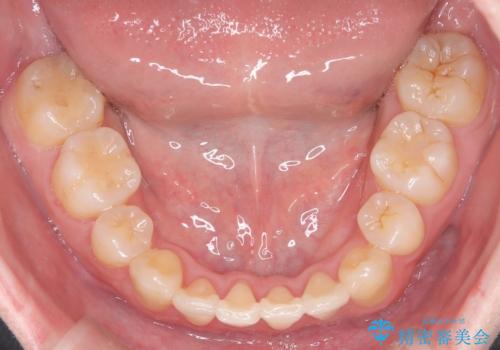

【重度叢生ワイヤー矯正】きれいな歯並びにしたい

- きれいな歯並びにしたいとの希望を持って来院された患者様です。

上下左右小臼歯を抜歯する治療計画を立て審美装置にて治療を行いました。

骨格的3級傾向もあり、咬合関係を仕上げるのに時間がかかりましたが、患者様には大変満足していただけました。

難しいケースでしたが、矯正用アンカースクリューを用いながら、臼歯関係もきれいに仕上げることができました。